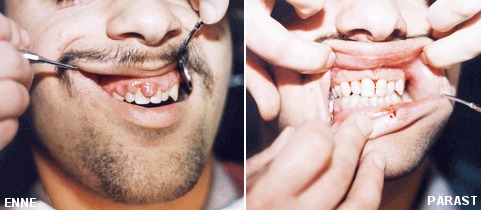

Hambakivi on mineraliseerunud (kivistunud, kõva) hambakatt. Hambakatt võib toidu- ja tubakapigmentide toimel suhteliselt lihtsalt värvuda, omandades kollakas-pruuni kuni mustja värvuse. Üksikutel juhtudel võib hambakivi plaadina hammaste mälumispind katta. Hamba vabal pinnal on hambakivi kergesti märgatav ning hõlpsalt instrumentide abil eemaldatav. Seevastu igeme alla juure pinnale ladestunud hambakivi on reeglina tihe, tume ning raskesti eemaldatav.

Hamba pinnal nähtav hambakatt kõvastub sülje soolade toimel hambakiviks.

Hambale moodustunud hambakivi ei eemaldu hambaharja abil.

Hambakivi eemaldamise all mõeldakse ladestiste eemaldamist hammastelt ja igemetaskust. Kõige sagedamini esineb hambakivi alumiste lõikehammaste ehk intsisiivide keelepoolsel pinnal, aga ka ülemiste mälumishammaste põskmisel pinnal, mõnikord aga ulatuslikult üle kogu hammaskonna. Hambakivi eemaldamine toimub spetsiaalse ultrahelil töötava seadeldisega, mis hamba pinda puudutades “väristab” sinna kinnitunud ladestise hambast lahti. Edasi toimub väiksemate ladestise jääkide eemaldamine käsiinstrumentidega ning kõige lõpuks hambapinna poleerimine lihvimiskivikeste ja -kummidega ning profülaktilise pastaga.